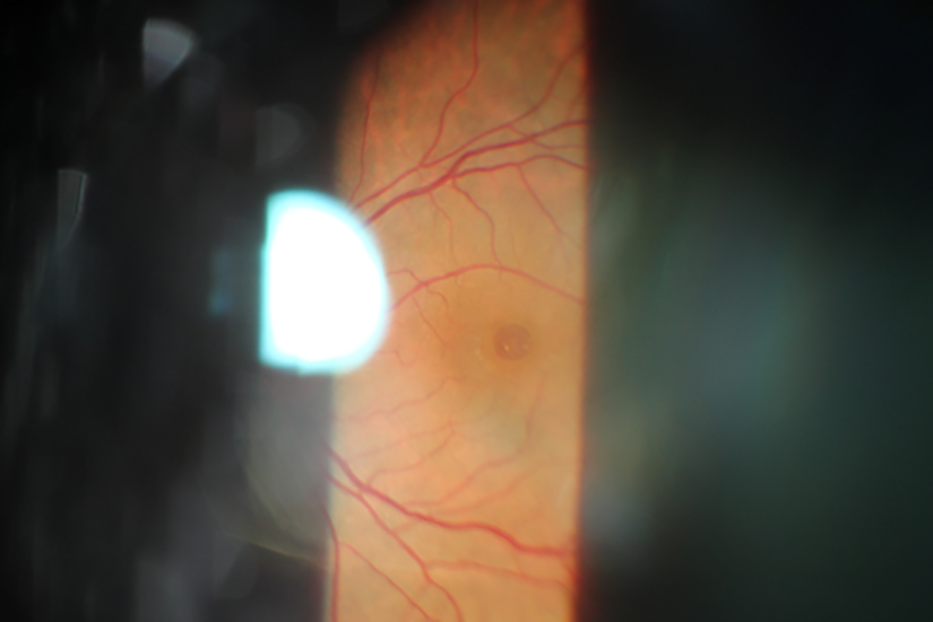

La parte delantera del ojo contiene un lente llamado cristalino que enfoca las imágenes en el interior del globo ocular. Esta zona, llamada retina, está cubierta por células nerviosas especiales que reaccionan a la luz. Estas células nerviosas están muy juntas entre ellas en el medio de la retina donde el ojo enfoca las imágenes que ve. Esta parte central de la retina se llama mácula y se encarga de la visión de detalles y colores.

A veces las células nerviosas de la mácula se separan las unas de las otras y se desplazan de la parte posterior del ojo. A esto se le llama agujero macular.